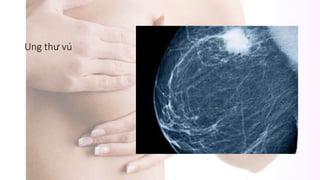

Ung thư vú